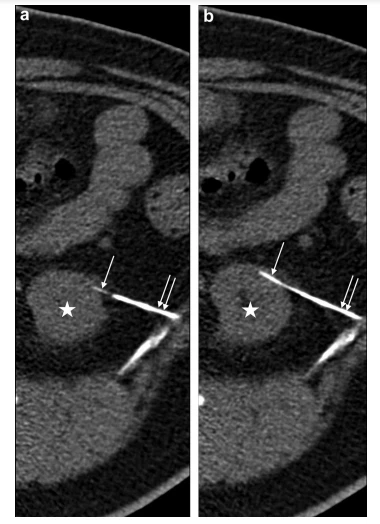

تم قياس حجم الكلى على التصوير بالرنين المغناطيسي لتحديد جرعة الخلية (3-8 مل). تم إجراء حقن الخلية باستخدام توجيه التصوير المقطعي (CT). تم إدخال إبرة توجيهية خارجية بمعيار محوري 20- (COOK، Inc، Bloomington، Indiana) في الحمة تحت المحفظة للقطب السفلي للكلية التي تم خزعةها سابقًا ، و 25- إبرة الحقن الداخلية للمقياس ({{ 4}}. قطر 51 مم ، IMD Inc ، هانتسفيل ، يوتا) في القشرة الكلوية ، في حدود 5 مم من الكبسولة (الشكل 1). بالنسبة للمرضى الذين تم حقنتهم لاحقًا ، تم إجراء العملية في نفس الكلية لمدة 6 أشهر. تم تنفيذ جميع الإجراءات من قبل أخصائيي الأشعة التداخلية ذوي الخبرة الذين تلقوا التدريب والمراقبة في الموقع. خضع المرضى للتخدير الواعي وخرجوا من وحدة الجراحة النهارية بعد الشفاء.

الشكل 1. تُظهر الصور المحورية للتصوير المقطعي المحوسب ذات الإسقاط الأقصى للشدة المائلة 49- ذكرًا يبلغ من العمر 49- عامًا مصابًا بداء السكري من النوع 2 ومرض كلوي مزمن يخضع لحقن الخلايا السلفية الكلوية الذاتية المتجانسة في القشرة الكلوية اليسرى. (أ) يتم وضع إبرة توجيه خارجية قياس 20- محورية (أسهم مزدوجة) في قشرة الكلية اليسرى (نجمة) ، وإبرة داخلية قياس 25- (سهم واحد) متطورة داخل المحفظة تحت المحفظة حمة. (ب) تم إدخال 25- الإبرة الداخلية G (السهم الفردي) بشكل أكبر من خلال 20- الإبرة الخارجية G (الأسهم المزدوجة) في القشرة ، مع وضع الطرف على بعد 5 مم تقريبًا من كبسولة اليسار يتم حقن الكلى (النجمية) والخلايا السلفية الكلوية الذاتية المتجانسة.

تضمن هذا التحليل 87 حقنة خلية في 51 مريضا (الجدول 1). تم إكمال تسعة وستين حقنة في 41 مريضًا و 18 حقنة في 1 {{2 {23}}} مريض يعانون من معدلات eGFRs 2 0 إلى 5 0 مل / دقيقة لكل 1.73 م 2 (RMCL {{12) }}) و 14 إلى 2 0 مل / دقيقة لكل 1.73 م 2 (REGEN -003) ، على التوالي. ظل جميع المرضى مستقرين ديناميكيًا طوال العملية. كانت جميع الحقن الموضعية في القشرة الكلوية ناجحة من الناحية الفنية ، ووثقت الأشعة المقطعية مواقع الإبرة النهائية في القشرة الكلوية تحت المحفظة (الشكل 1). لا توجد فروق ذات دلالة إحصائية في الهيموجلوبين (P ¼ 0. 3 [RMCL -002 ، الحقن الأول] ، P ¼ 0. 2 [RMCL -002 ، الحقن الثاني] ، P ¼ 0. 2 [REGEN -003 ، الحقن الأول] ، P 0.14 [REGEN -003 ، الحقن الثاني]) والهيماتوكريت (P ¼ 0.2 [RMCL002 ، الحقن الأول] ، P ¼ 0.3 [RMCL -002 ، الحقن الثاني] ، P 0.3 [REGEN -003 ، الحقن الأول] ، P> 0.9 [REGEN -003 ، الحقن الثاني]) بين الخلية السابقة واللاحقة الحقن (الجدول 2). الاختلافات في الكرياتينين ، نيتروجين اليوريا في الدم ، و eGFR لم تكن كبيرة أيضًا (الجدول 2 ، الشكل 2). لم يكن هناك أي نزيف متعلق بالإجراء أو تسرب للخلايا موثق أثناء الحقن الموجه بالتصوير المقطعي المحوسب. ومع ذلك ، فإن الورم الدموي المتأخر تحت المحفظة الذي يتطلب دخول المستشفى دون نقل الدم كان موجودًا في الموجات فوق الصوتية بعد الحقن في مريضة (1/1 بالمائة [1 من 87 مريضًا]) مع معدل الترشيح الكبيبي من 15 مل / دقيقة لكل 1.73 م 2 (REGEN {{59) }}).